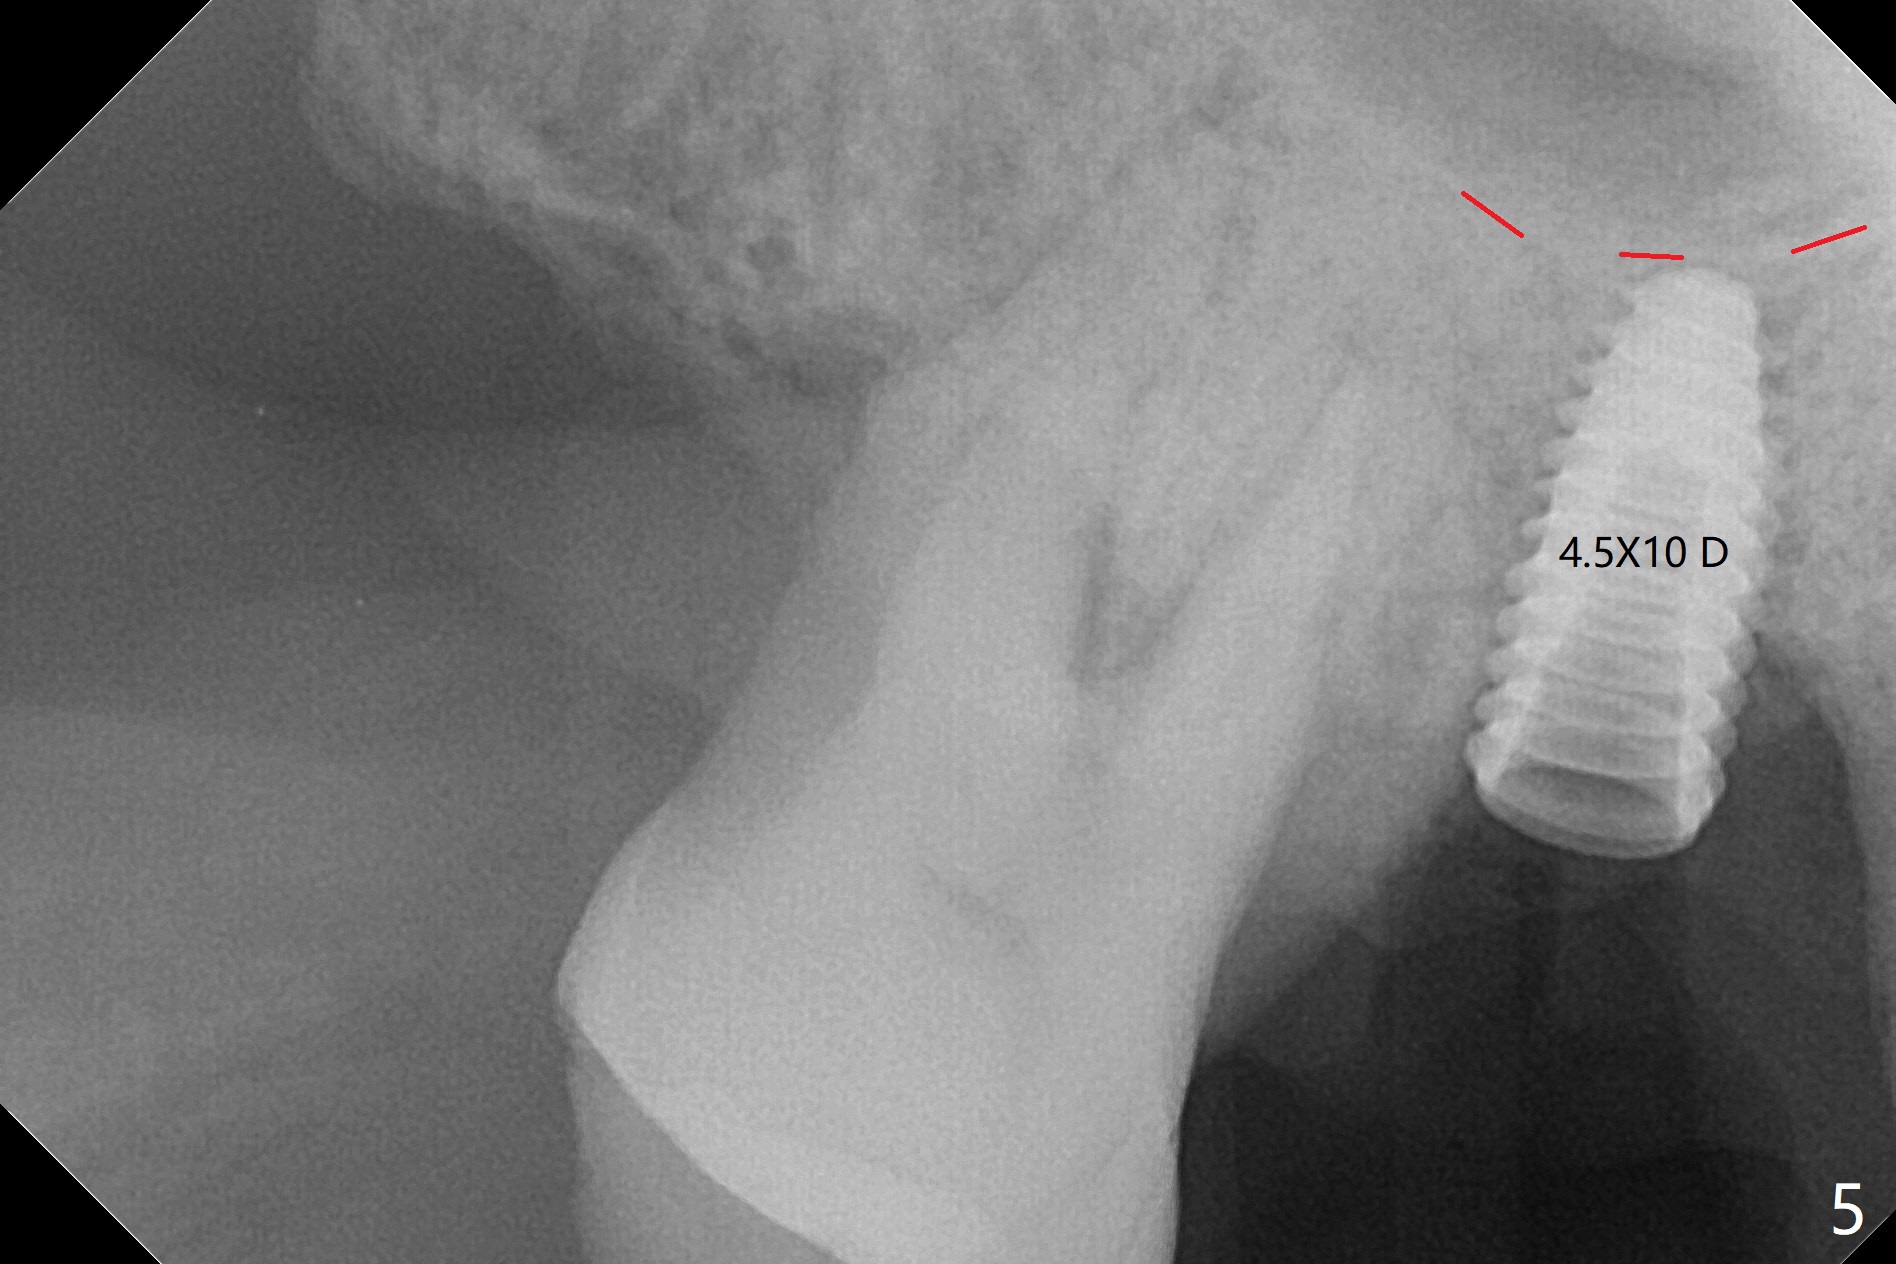

53岁男吸烟,牙周炎,咬合力大,3号牙颊侧(图一),腭侧(图二:P)牙龈退缩,尤其是近中颊侧根(图一:MB),拔牙后,中隔冠方(表面)有好像健康的牙龈(图三:*),近中,远中连接处切开(图三:虚线),将中隔牙龈推向近中颊侧牙槽窝(图四:箭头),修复退缩牙龈,而且暴露下面中隔(S),接着在它上面导板钻洞,避免软组织创伤。利用报废植体试图内提升(图五(红虚线:窦底)),最终正式植体完成提升(图六:黑*),初步在牙槽窝深部放置粘性骨粉(白*)后,放入基台,之后再次在植体,基台周围放置骨粉(图七:*),最后借助临时牙冠(图八,九:T)和外衬里(图八:R)封闭牙槽窝开口,G是近中颊侧迁移的牙龈。植体垂直进入上颌窦可以减少窦膜破裂(图五,六,九),术后没有鼻出血。术后1个月临时牙冠松动,去除牙冠和基台,安置愈合帽(图十)。表面骨粉遗失,但是颊侧移位的中隔牙龈好像帮助软组织预后。